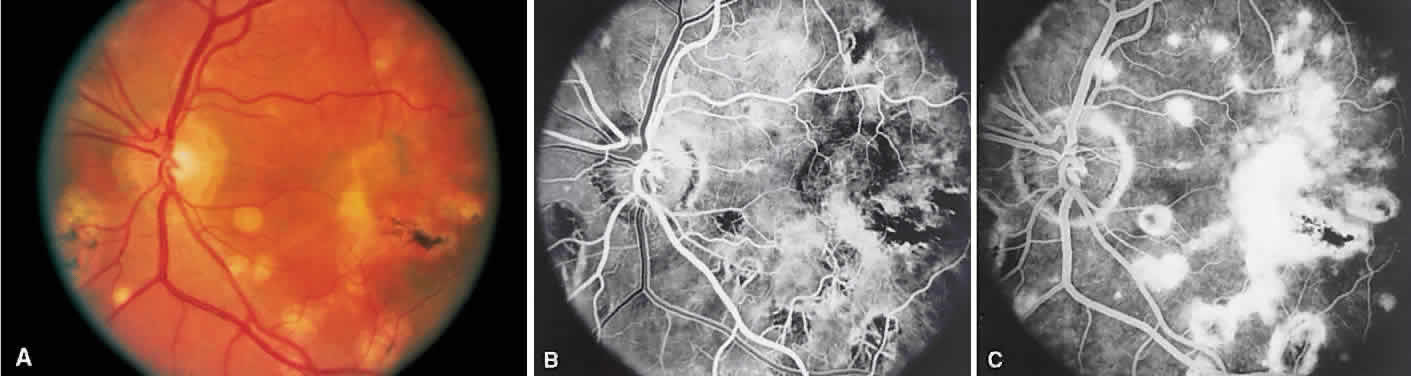

Vogt-Koyanagi-Harada syndrome, also known as uveomeningoencephalitis syndrome, is a systemic disease often found in young, darkly pigmented whites, blacks, native Indians, Hispanics, and Asians. It presents as an anterior and posterior uveitis with disc hyperemia, disc edema, and exudative retinal detachment (Figs. 2A and B and 3A). Systemic signs and symptoms include headache, hearing loss, poliosis, vitiligo, nuchal rigidity, seizures, and even coma. SRNV and disciform scars are late complications. The differential diagnosis should include AMPPPE and sympathetic ophthalmia.

Fig. 2. Vogt-Koyanagi-Harada syndrome. (A) Fundus photograph of the right eye and (B) the left eye showing bullous retinal detachments. (C) Fluorescein angiogram showing multiple hyperfluorescent leaks at the level of the retinal pigment epithelium. (D) Multiple coalescing leaks and fluorescein staining of the subretinal fluid. Large areas of hyperfluorescence involving the entire right posterior pole due to pooling of dye beneath the subretinal space.

Fig. 3. Vogt-Koyanagi-Harada syndrome. A. Fundus photograph of the left eye showing multifocal serous retinal detachment. B. Late fluorescein angiogram showing pooling of dye in the areas of serous detachment. C. Indocyanine angiography showing areas of blocked fluorescence corresponding to serous detachment. More areas of hypofluorescence are noted than those observed on fluorescein angiogram.

There is a characteristic fluorescein angiographic appearance in the early phase showing multiple discrete hyperfluorescent dots at the retinal pigment epithelial level that enlarge over time (see Fig. 2C and D). In the late phase, if there is a serous detachment, the fluorescein pools beneath the subretinal space (see Fig. 3B). The edematous disc hyperfluoresces in the late phase. Generally, the retinal vessels are unaffected.7,8 Retinochoroidal anastomoses also have been documented by fluorescein angiography.9

ICG angiography shows multiple hypofluorescent spots in the posterior pole (see Fig. 3C). These spots may coalesce and obscure the filling of large choroidal vessels. When serous retinal detachment develops, the marked hyperfluorescence observed on FA is not as prominently noted in ICG angiography, presumably because of the highly protein-bound nature of ICG. In fact, diffuse late hypofluorescence may be observed in patients with serous retinal detachment.10 Ill-defined areas of hyperfluorescence corresponding to diffuse choroidal staining may be seen in some cases in the late phases of the angiogram. The optic disc may stain with ICG in the acute phase but usually is minimal compared to that observed on FA.